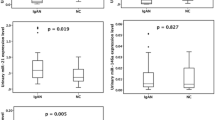

Urinary exosomal miR-16-5p, miR-26b-3p, miR-29a-3p, miR-29c-3p, miR-126-3p, miR-199a-3p, miR-615-3p, and miR-29b-3p levels were dysregulated in the IgAN group compared to those in the normal control group (Fig. 2). The expression level of miR-29b-3p in the IgAN group was significantly lower than that in the MGN group (Fig. 2).

Figure 3 shows the negative correlation between the levels of most urinary exosomal miRNAs (miR-16-5p, miR-29a-3p, miR-124-3p, miR-126-3p, miR-199a-3p, miR-199b-5p, miR-335-3p, and miR-615-3p) and eGFR in IgAN patients. The levels of 10 selected urinary exosomal miRNA showed a positive correlation with uPCR, except for miR-615-3p (Fig. 4).